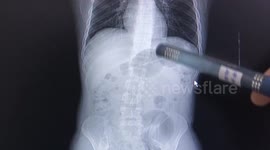

But soon after he was sick and after becoming more unwell Rebecca took Rylo to the vets, where an x-ray revealed a 12in plastic arrow inside his stomach.

"They x-rayed him and rang me to say that I was not going to believe what the problem was," Rebecca said. "

"I was in total shock when it happened. I couldn't believe how he behaved with a 12-inch arrow in him."